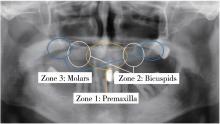

Figure 1

Division of edentulous maxilla by Bedrossian"